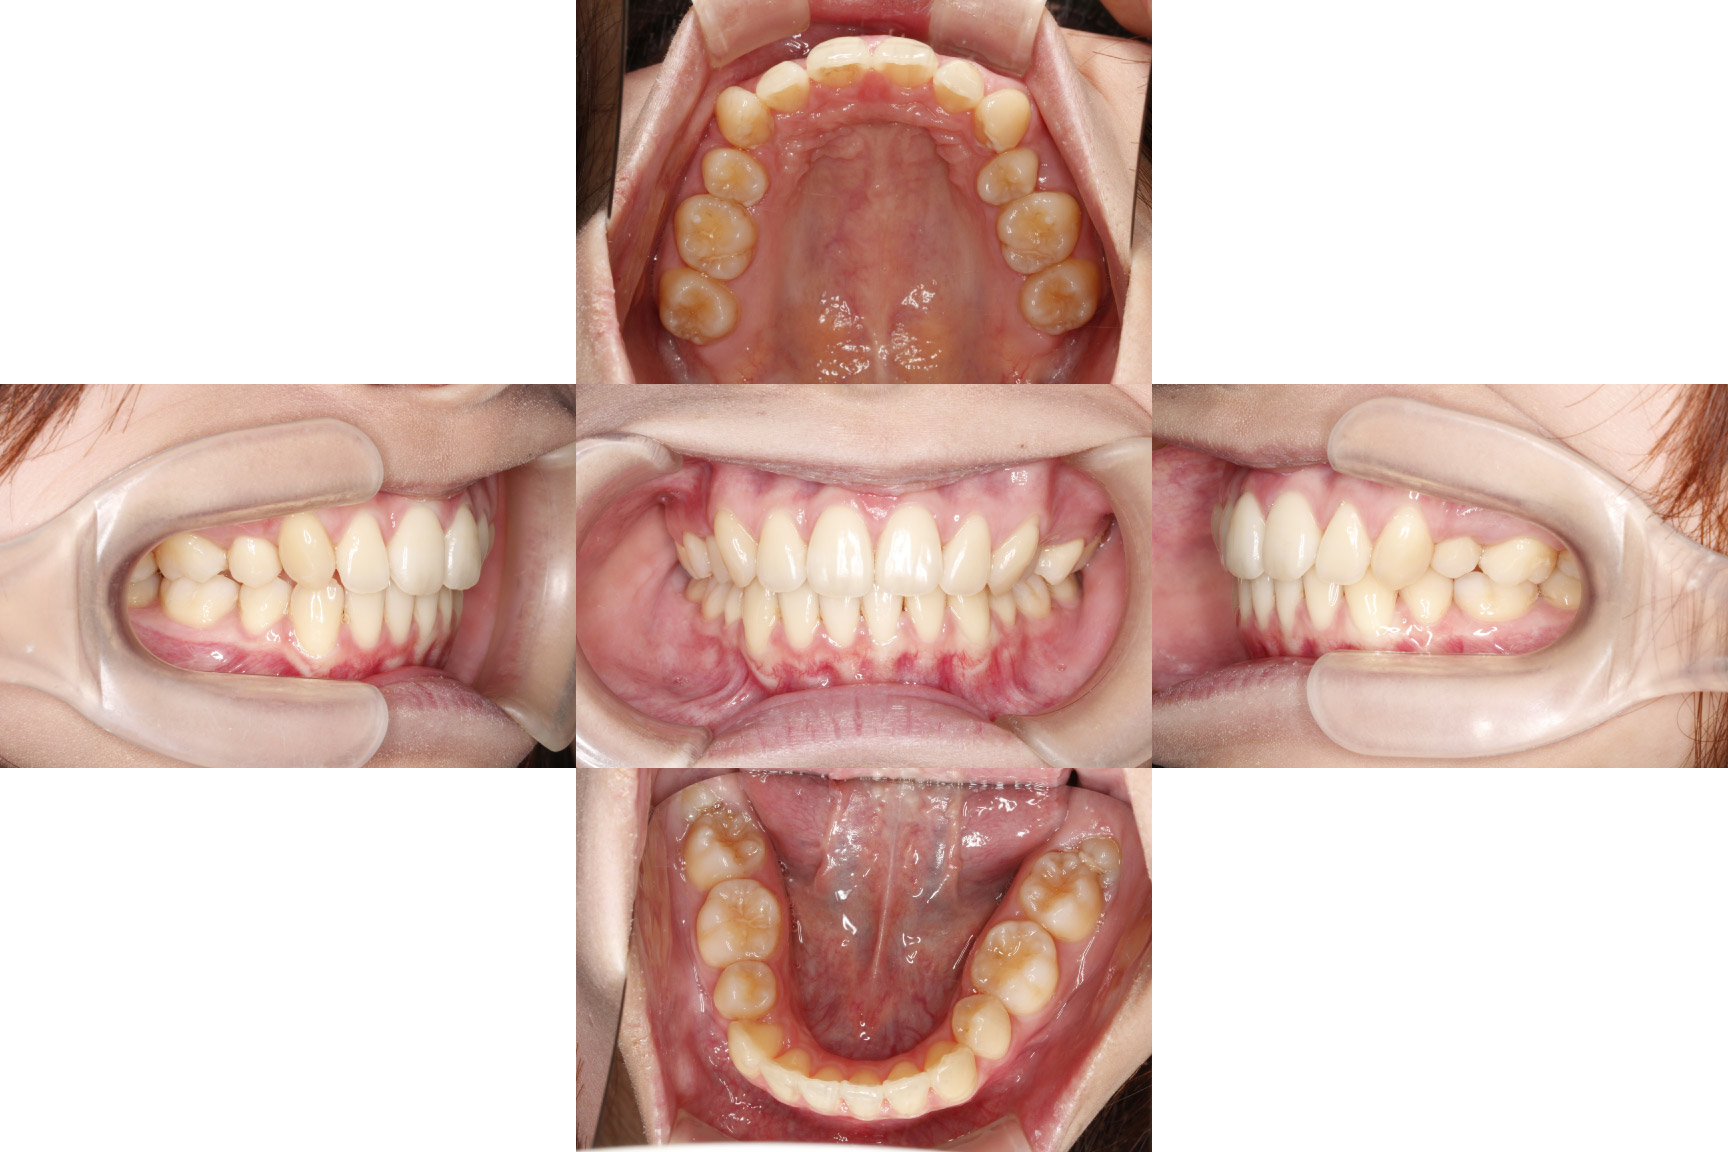

2年8か月経過